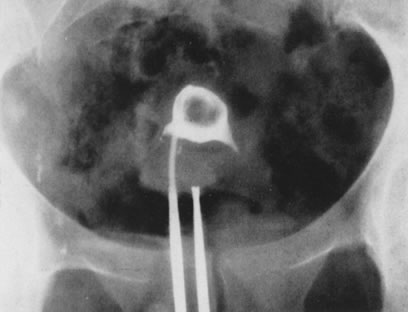

Using the resectoscope and a special electrode, the endometrium may be resected or coagulated. The initial technique to accomplish endometrial destruction was resection with use of the loop electrode. The difficulty in maintaining a uniform depth of resection makes this technique cumbersome, however. Furthermore, because resection could predispose to more fluid intravasation and immediate postoperative bleeding, physicians were prompted to use the alternative method of endometrial coagulation with thicker roller-bar or roller-ball electrodes, which can accomplish endometrial destruction just by coagulation. This technique is simpler, faster, and as effective as resection, and the instrumentation and electrical power units required are less expensive than those required for laser ablation. In general, pure coagulating current of 40 to 50 W or, alternatively, pure cutting current of 100 to 120 W, can be used to accomplish this procedure. Because the electrical current used is unipolar, grounding of the patient is necessary to complete the electrical circuit, and no electrolytes should be used with the distending media. The possibility of fluid overload and water intoxication must be carefully monitored, measuring precisely the inflow and outflow of fluids used and deducting the deficit of fluid not recovered.67–74

The results obtained with endometrial ablation by electrosurgery are similar to those achieved with lasers. Nonetheless, it seems that the failure rate is slightly higher (5% to 10%), as one would expect, because electrosurgery may not be as predictable as the laser energy, particularly when visual appraisal of the thermal damage cannot predict uterine wall penetration (Fig. 38).66,74,75

Fig. 38. Endometrial ablation with a roller-bar electrode. A. Line of demarcation can be seen between treated and nontreated area. B. Completed procedure.